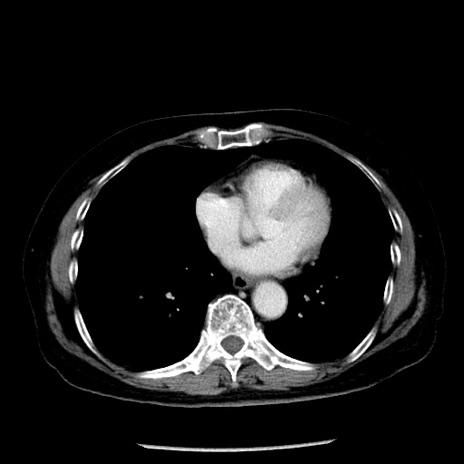

冠状断像